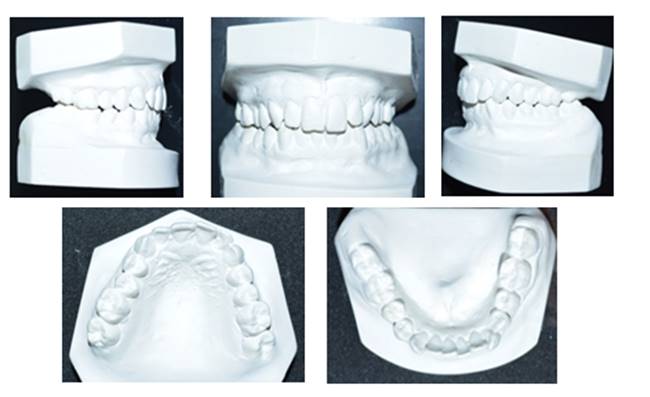

Methods: The clinical examination included extra-oral and intra-oral photographs, panoramic radiographic, lateral cephalometric, stone casts, and upper and lower arch analysis obtained from ClinCheck 3.0.The treatment planning was resolved the crowding in both upper and lower arches and the severe rotation of 33 tooth (46°) using Invisalign system as well as the canine and molar relationship, dental verticalization, adequate over jet, overbite and dental midline using the same system. The duration of the treatment was approximately eight months.

Results: In Post-treatment extra oralphotographs, no significant changes were observed at the end of the treatment. Intraoral photographs showed an important and notable improved aesthetics. The canine relationship improved slightly and molar Class Irelationship was maintained. An increase in transverse diameter was observed at the level of first premolars, second premolars and first molars. The overbite was improved. The crowding and the severe canine rotation were corrected. No obvious root resorption was radiographically evident and slight cephalometric changes.